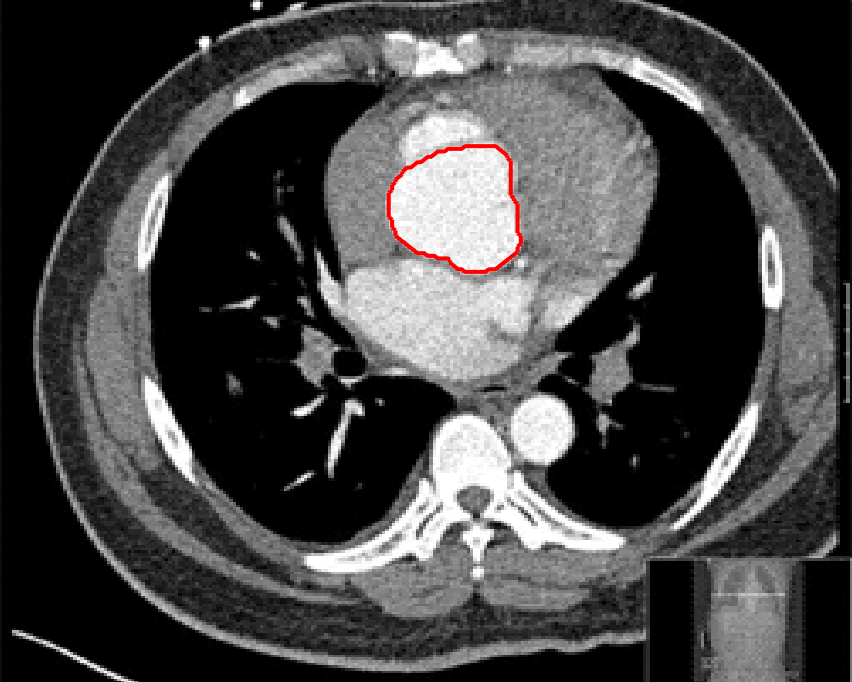

Four sets of test results are shown below. In Test 1 we compare models M1 – M6 to the proposed model M7 for two images which are hard to segment. The first is a CT scan from which we would like to segment the lower portion of the heart, the second is an MRI scan of a knee and we would like to segment the top of the Tibia. See Figure 9 for the test images and the marker sets used in the experiments. In Test 2 we will review the sensitivity of the proposed model to the main parameters. In Test 3 we will give several results achieved by the model using marker and anti-marker sets. In Test 4 we show the initialisation independence and marker independence of the Geodesic Model on real images.

In this test we give the segmentation results for models M1 – M7 for the two challenging test images shown in Figure 9. The marker and anti-marker sets used in the experiments are also shown in this figure. After extensive parameter tuning, the best final segmentation results for each of the models are shown in Figures 10 and 11. For M1 – M4 we obtain incorrect segmentations in both cases. In particular, the results of M2 and M4 are interesting as the former gives poor results for both images, and the latter gives a reasonable result for Test Image 1 and a poor result for Test Image 2. In the case of M2, the regularisation term includes the edge detector and the distance penalty term (see (4)). It is precisely this which permits the poor result in Figures 10(b) and 11(b) as the edge detector is zero along the contour and the fitting terms are satisfied there (both intensity and area constraints) – the distance term is not large enough to counteract the effect of these. In the case of M4, the distance term and edge detector are separated from the regulariser and are used to weight the Chan-Vese fitting terms (see (9)). The poor segmentation in Figure 11(b) is due to the Chan-Vese terms encouraging segmentation of bright objects (in this case), weighting enforces these terms at all edges in the image and near . In experiments, we find that M4 performs well when the object to segment is of approximately the highest or lowest intensity in the image, however when this is not the case, results tend to be poor. We see that, in both cases, models M5 and M6 give much improved results to M2 and M4 (obtained by incorporating the geodesic distance penalty into each). The proposed Geodesic Model M7 gives an accurate segmentation in both cases. It remains to compare M5, M6 and M7. We see that M5 is a non-convex model (and cannot be made convex [39]), therefore results are initialisation dependent. It also requires one more parameter than M6 and M7, and an accurate set to give a reasonable area constraint in (4). These limitations lead us to conclude M6 and M7 are better choices than M5. In the case of M6, it has the same number of parameters as M7 and gives good results. M6 can be viewed as the model M7 with weighted intensity fitting terms (compare (18) and (30)). Experimentally, we find that the same quality of segmentation result can be achieved with both models generally, however M6 is more parameter sensitive than M7. This can be seen in the parameter map in Figure 12 with M7 giving an accurate result for a wider range of parameters than M6. To show the improvement of M7 over previous models, we also give an image in Figure 13 which can be accurately segmented with M7 but the correct result is never achieved with M6 (or M3). Therefore we find that M7 outperforms all other models tested M1 – M6.

(i) (ii) (iii) (iv)